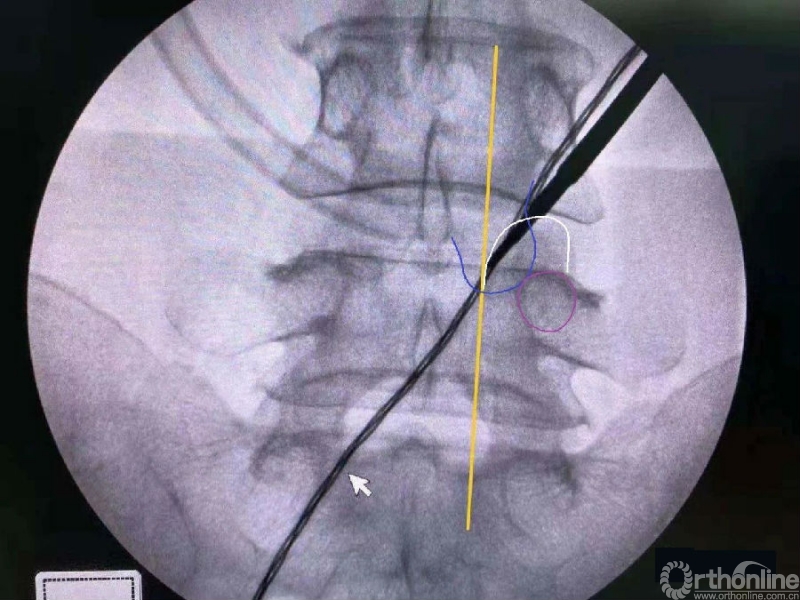

第二次定位虽然并位于椎弓根内缘线上,但是我们觉得本病历参考内缘线的话可能会把下关节突的2/3磨掉,所以我们选择第二个接近椎弓根内缘线的定位孔作为镜下下关节突内缘切除的外界。

术中切除下关节突内缘的范围